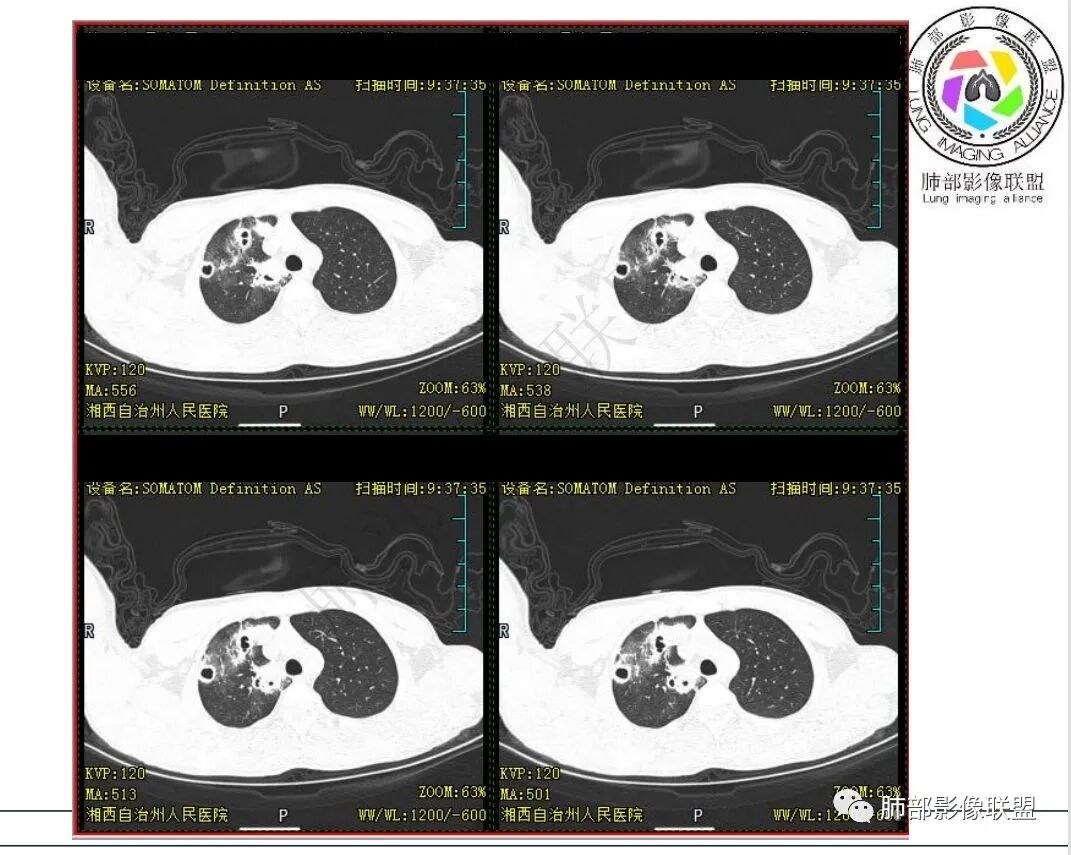

临床:男,15岁,咳嗽咳痰伴咯血盗汗10余天。既往有结核病患接触史。

实验室:血沉增高,淋巴细胞稍低,其他无特殊。

影像:右肺上叶多发实变影结节影,边界模糊,边缘收缩,伴多发空洞,洞壁光滑,部分支气管壁增厚。

1.青少年男性,急性起病,咳嗽咳痰伴咯血盗汗10余天。既往有结核病患接触史。

2.实验室:血沉增高,淋巴细胞稍低,其他无特殊。

3.首次CT提示:右肺上叶多发结节影及实变影,簇状分布,周围散在磨玻璃影,结节内多类圆形空洞,内壁光整,有一定张力,偶见液平。部分支气管壁增厚。

考虑良性感染性病变可能。